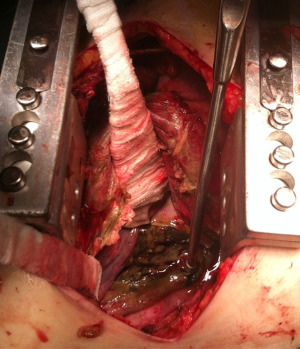

Injuries of upper and medium esophagus are usually approached by right thoracotomy (V intercostal space), while distal esophageal perforations are better managed through left thoracotomy (VI intercostal space). In the last years, the role of thoracoscopy for managing esophageal perforation has been improving, allowing a faster recovery of the patients (1,19). Surgical treatment consists of debridement of necrotic tissue and toilette of purulent material (Figure 1) to expose the perforation. In early treatment, the attempt of suture can be successful and requires a proximal and distal myotomy to expose the mucosal rupture, that must be repaired by interrupted absorbable suture. Then the esophageal muscle must be closed with another interrupted suture, better if buttressed with vascularized flap of intercostal muscle, diaphragmatic pedicle, pleural or omental graft (1,6). When a repair is not feasible, like in delayed context or in the setting of extensive necrotic tissue, a hybrid treatment can be attempted: after surgical toilette and drainage of mediastinum and pleural space, a stent or a nasoesophageal tube can be placed to avoid directly an esophageal resection or diversion. Several exclusion and diversion techniques are described (5). Conventionally, a proximal and distal diversion is performed to exclude the perforated tract and an end or side cervical esophagostomy is made. This technique requires a second stage of reconstruction. To eliminate the need of a second operation, a proximal esophageal ligation can be done with creation of a cervical esophageal mucosa fistula (side esophagostomy) (1).